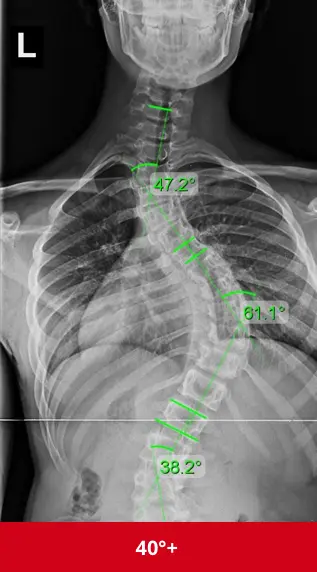

اعوجاج العمود الفقري الشديد: الخطورة في الدرجة وليس النوع

حتى الاعوجاج مجهول السبب (وهو الأكثر شيوعًا)، يمكن أن يصبح خطيرًا إذا كان شديد الدرجة.

متى يُعتبر شديدًا؟

عندما تتجاوز زاوية الانحناء 40–50 درجة

خاصة إذا استمر في التفاقم

لماذا يُعد خطيرًا؟

قد يؤثر على وظائف الرئة

يسبب آلامًا مزمنة

يؤدي إلى تشوه واضح في شكل الجسم

قد يتطلب جراحة إذا لم يُسيطر عليه

إذًا، الخطورة هنا ليست في الاسم، بل في شدة الانحناء وإهماله.

اعوجاج العمود الفقري الصدري الشديد: خطر على التنفس

من الأنواع التي تثير القلق أيضًا:

الاعوجاج الذي يصيب المنطقة الصدرية من العمود الفقري.

لماذا؟

لأن هذه المنطقة مرتبطة بالقفص الصدري

ومع زيادة الانحناء، يقل تمدد الرئتين

قد تظهر صعوبة في التنفس في الحالات المتقدمة

لهذا السبب، الاعوجاج الصدري الشديد يحتاج متابعة دقيقة، حتى لو لم يشتكِ المريض من أعراض في البداية.